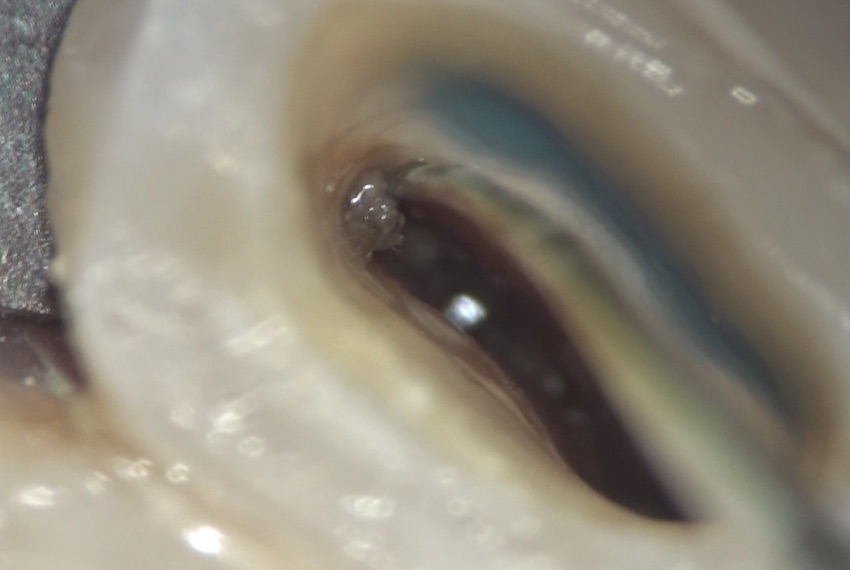

触ってみると・・・

中からは汚れが出て来ます。

隔壁を建て、ラバーダムをして、マイクロスコープで内部を見てみると・・・

さらに汚れが溜まっていました。